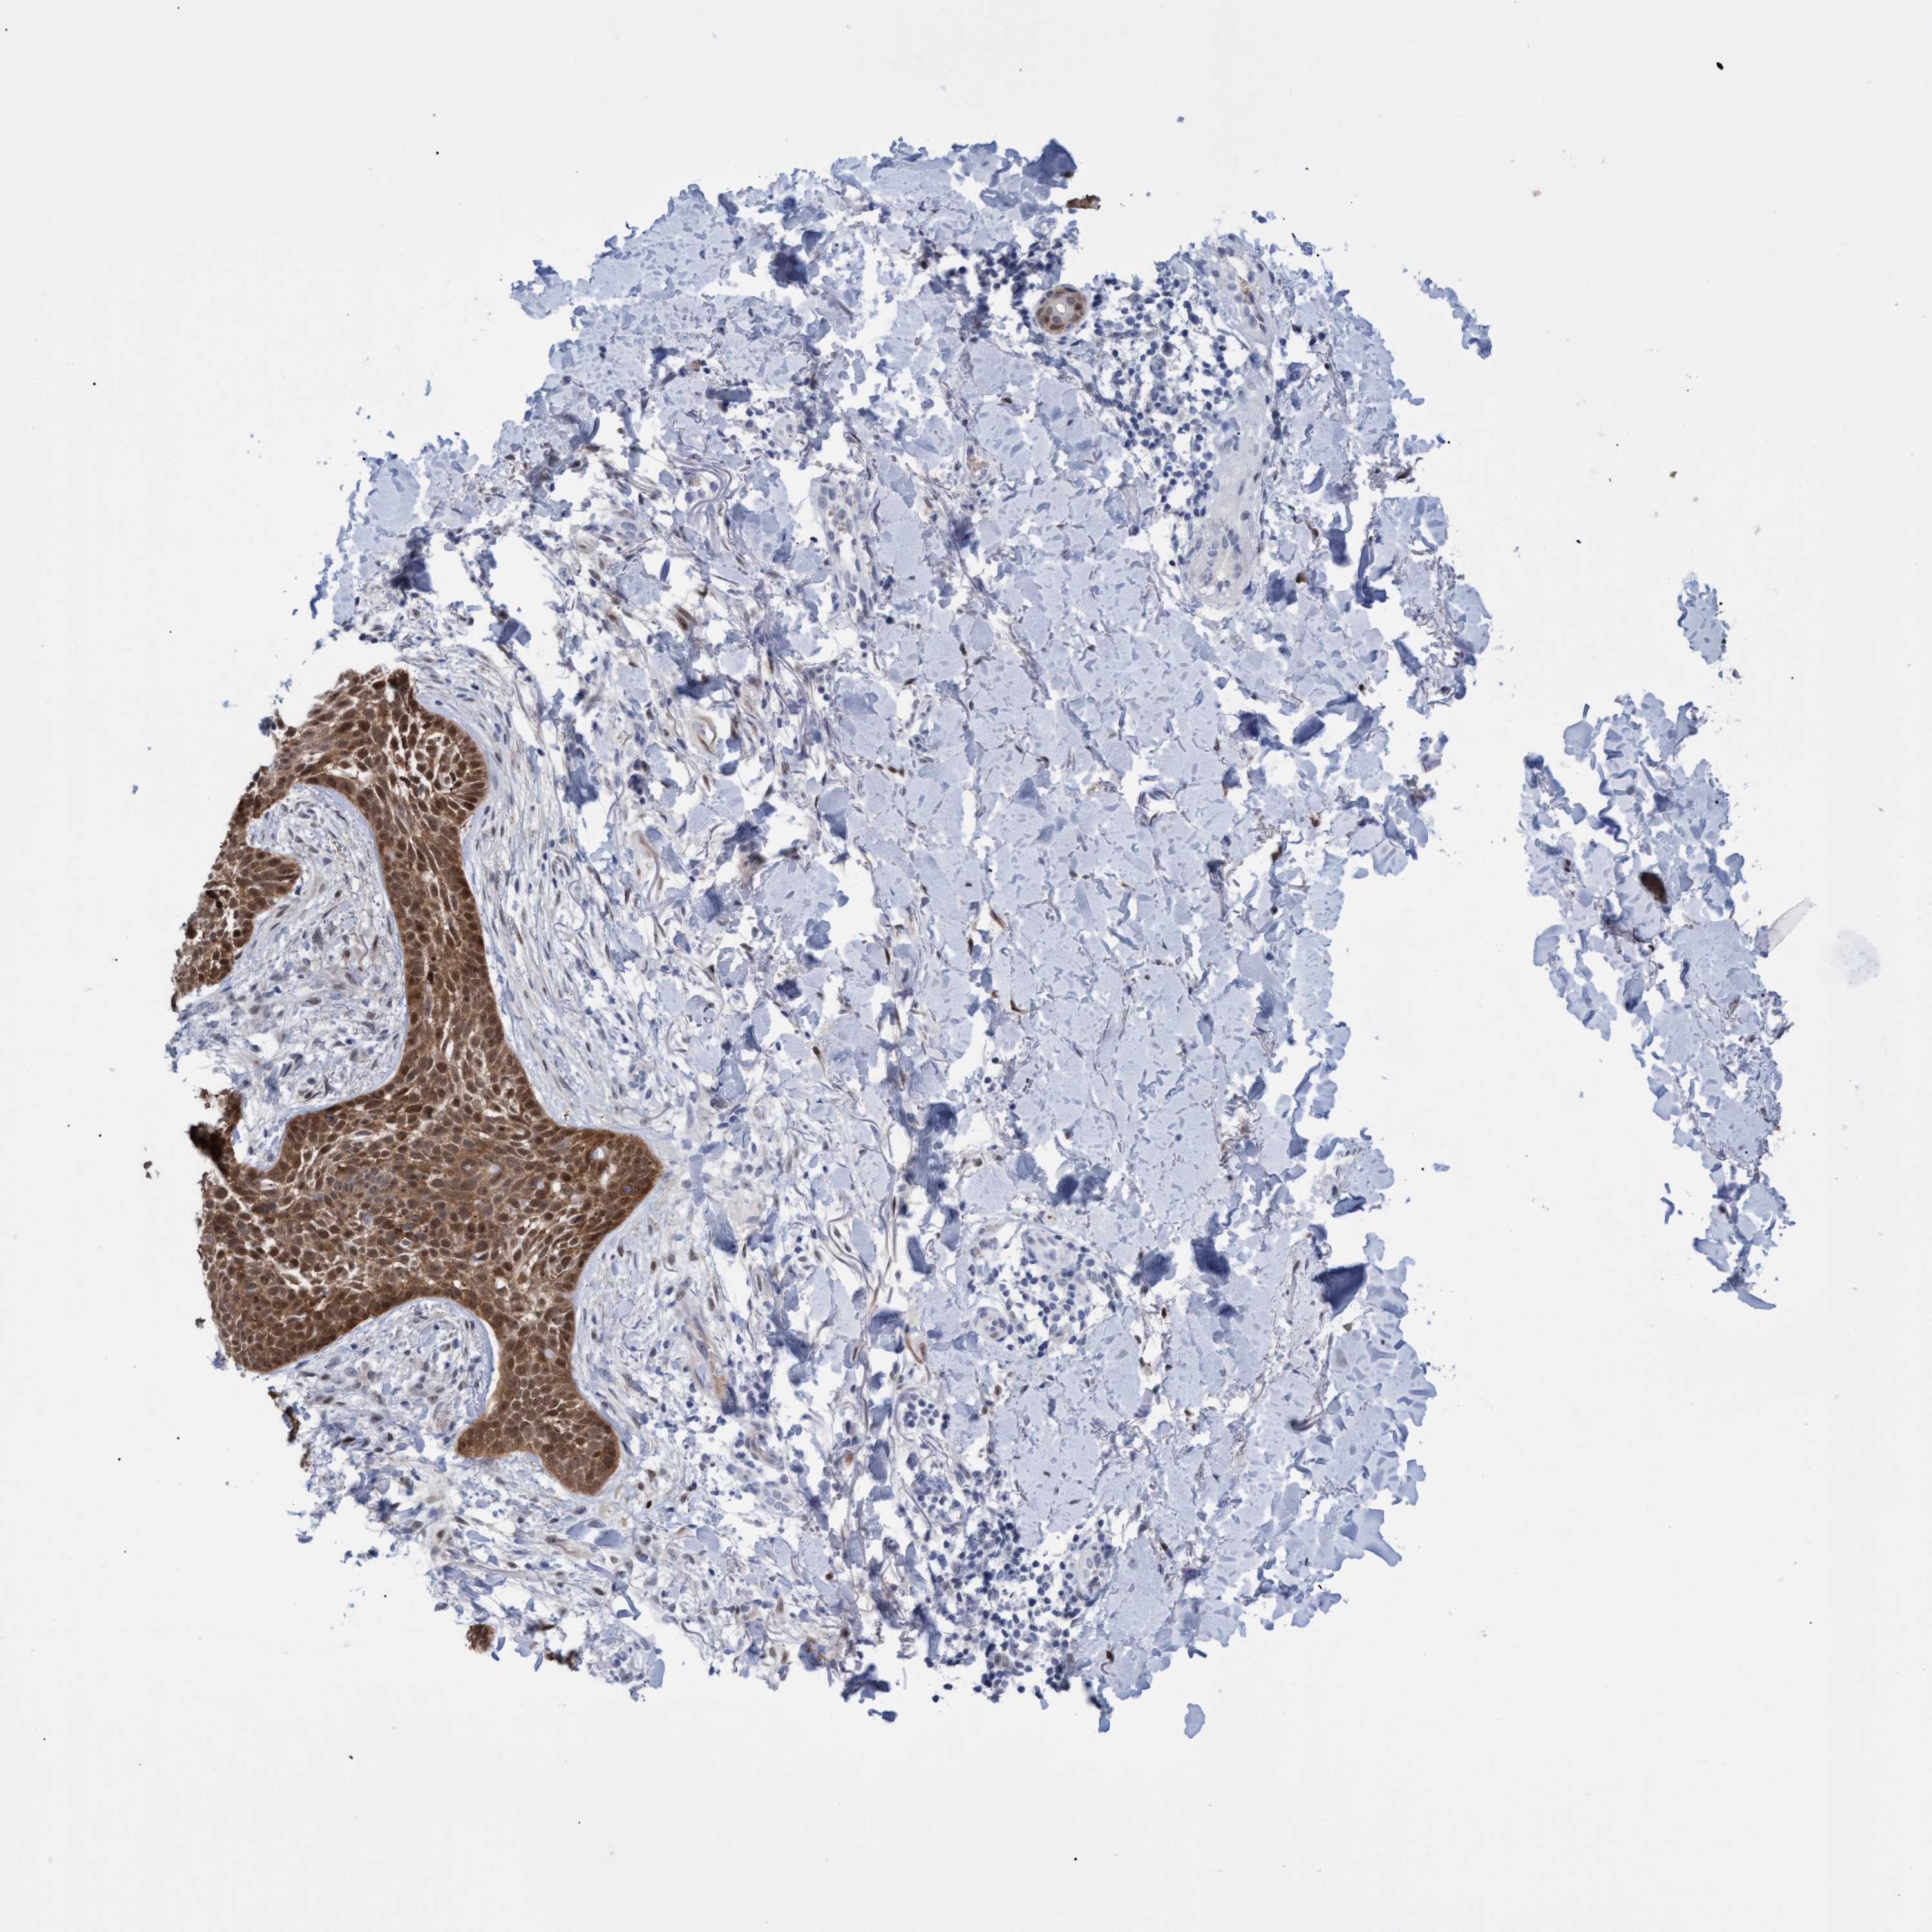

SKIN CANCER - Protein expressioni

A mouse-over function shows sample information and annotation data. Click on an image to view it in a full screen mode. Samples can be filtered based on level of antibody staining by selecting one or several of the following categories: high, medium, low and not detected. The assay and annotation is described here.

Antibody staining in the annotated cell types in the current human tissue is reported as not detected, low, medium, or high, based on conventional immunohistochemistry profiling in selected tissues. This score is based on the combination of the staining intensity and fraction of stained cells.

Each image is clickable and will lead to virtual microscopy that enables deeper exploration of all samples and also displays staining intensity scores, fraction scores and subcellular localization as well as patient and tissue information for each sample.

Antibody HPA023139

Basal cell carcinoma

Squamous cell carcinoma, NOS

Squamous cell carcinoma, metastatic, NOS